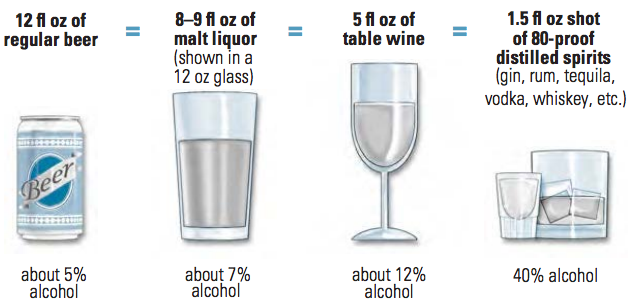

Drinking on occasion counts more to calorie consumption, sometimes even more than chronic drinkers. R

Increasing frequency and intensity of alcohol use is associated with statistically significant yet quantitatively small weight gain for men. R

Compared with non-drinkers, normal-weight women that consumed light-to-moderate amount of alcohol experienced less weight gain and lower risk of becoming overweight, which is a benefit, if you are a woman. R